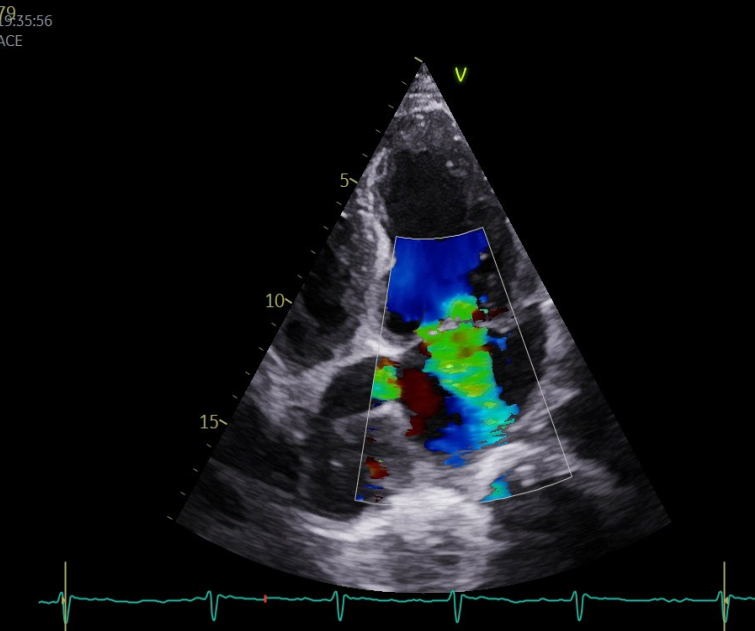

triplex kardias